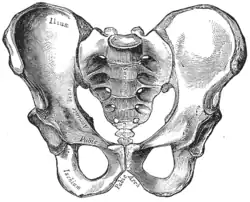

| Comparação entre uma pelve androide (esquerda) e uma ginecoide (direita). | |

A obstetrícia tradicional caracterizou quatro tipos de pelves:

- Ginecoide: forma ideal, com abertura superior arredondada a levemente oval (entrada obstétrica ligeiramente menos transversa).

- Androide: abertura triangular, espinhas isquiáticas proeminentes, arco púbico mais angulado.

- Antropoide: o maior diâmetro transverso é menor que o diâmetro obstétrico ântero-posterior.

- Platilipeloide: abertura superior achatada, com diâmetro obstétrico reduzido.